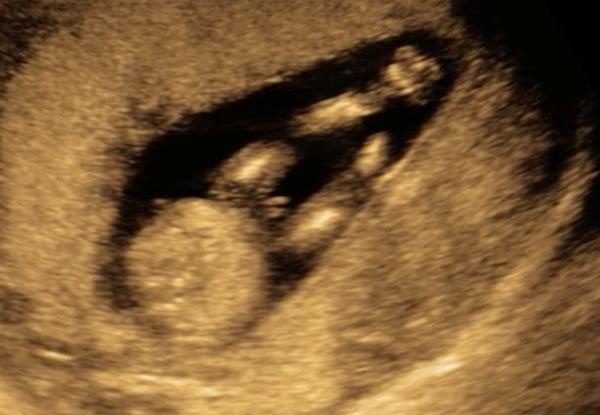

Fotky jsou výstřižky z videa 1. screeningu, 13+3 tt. 🙂

bohužel kvalita snímků a zachycené roviny se neumožňují k tomuto blíže vyjádřit. 🙂